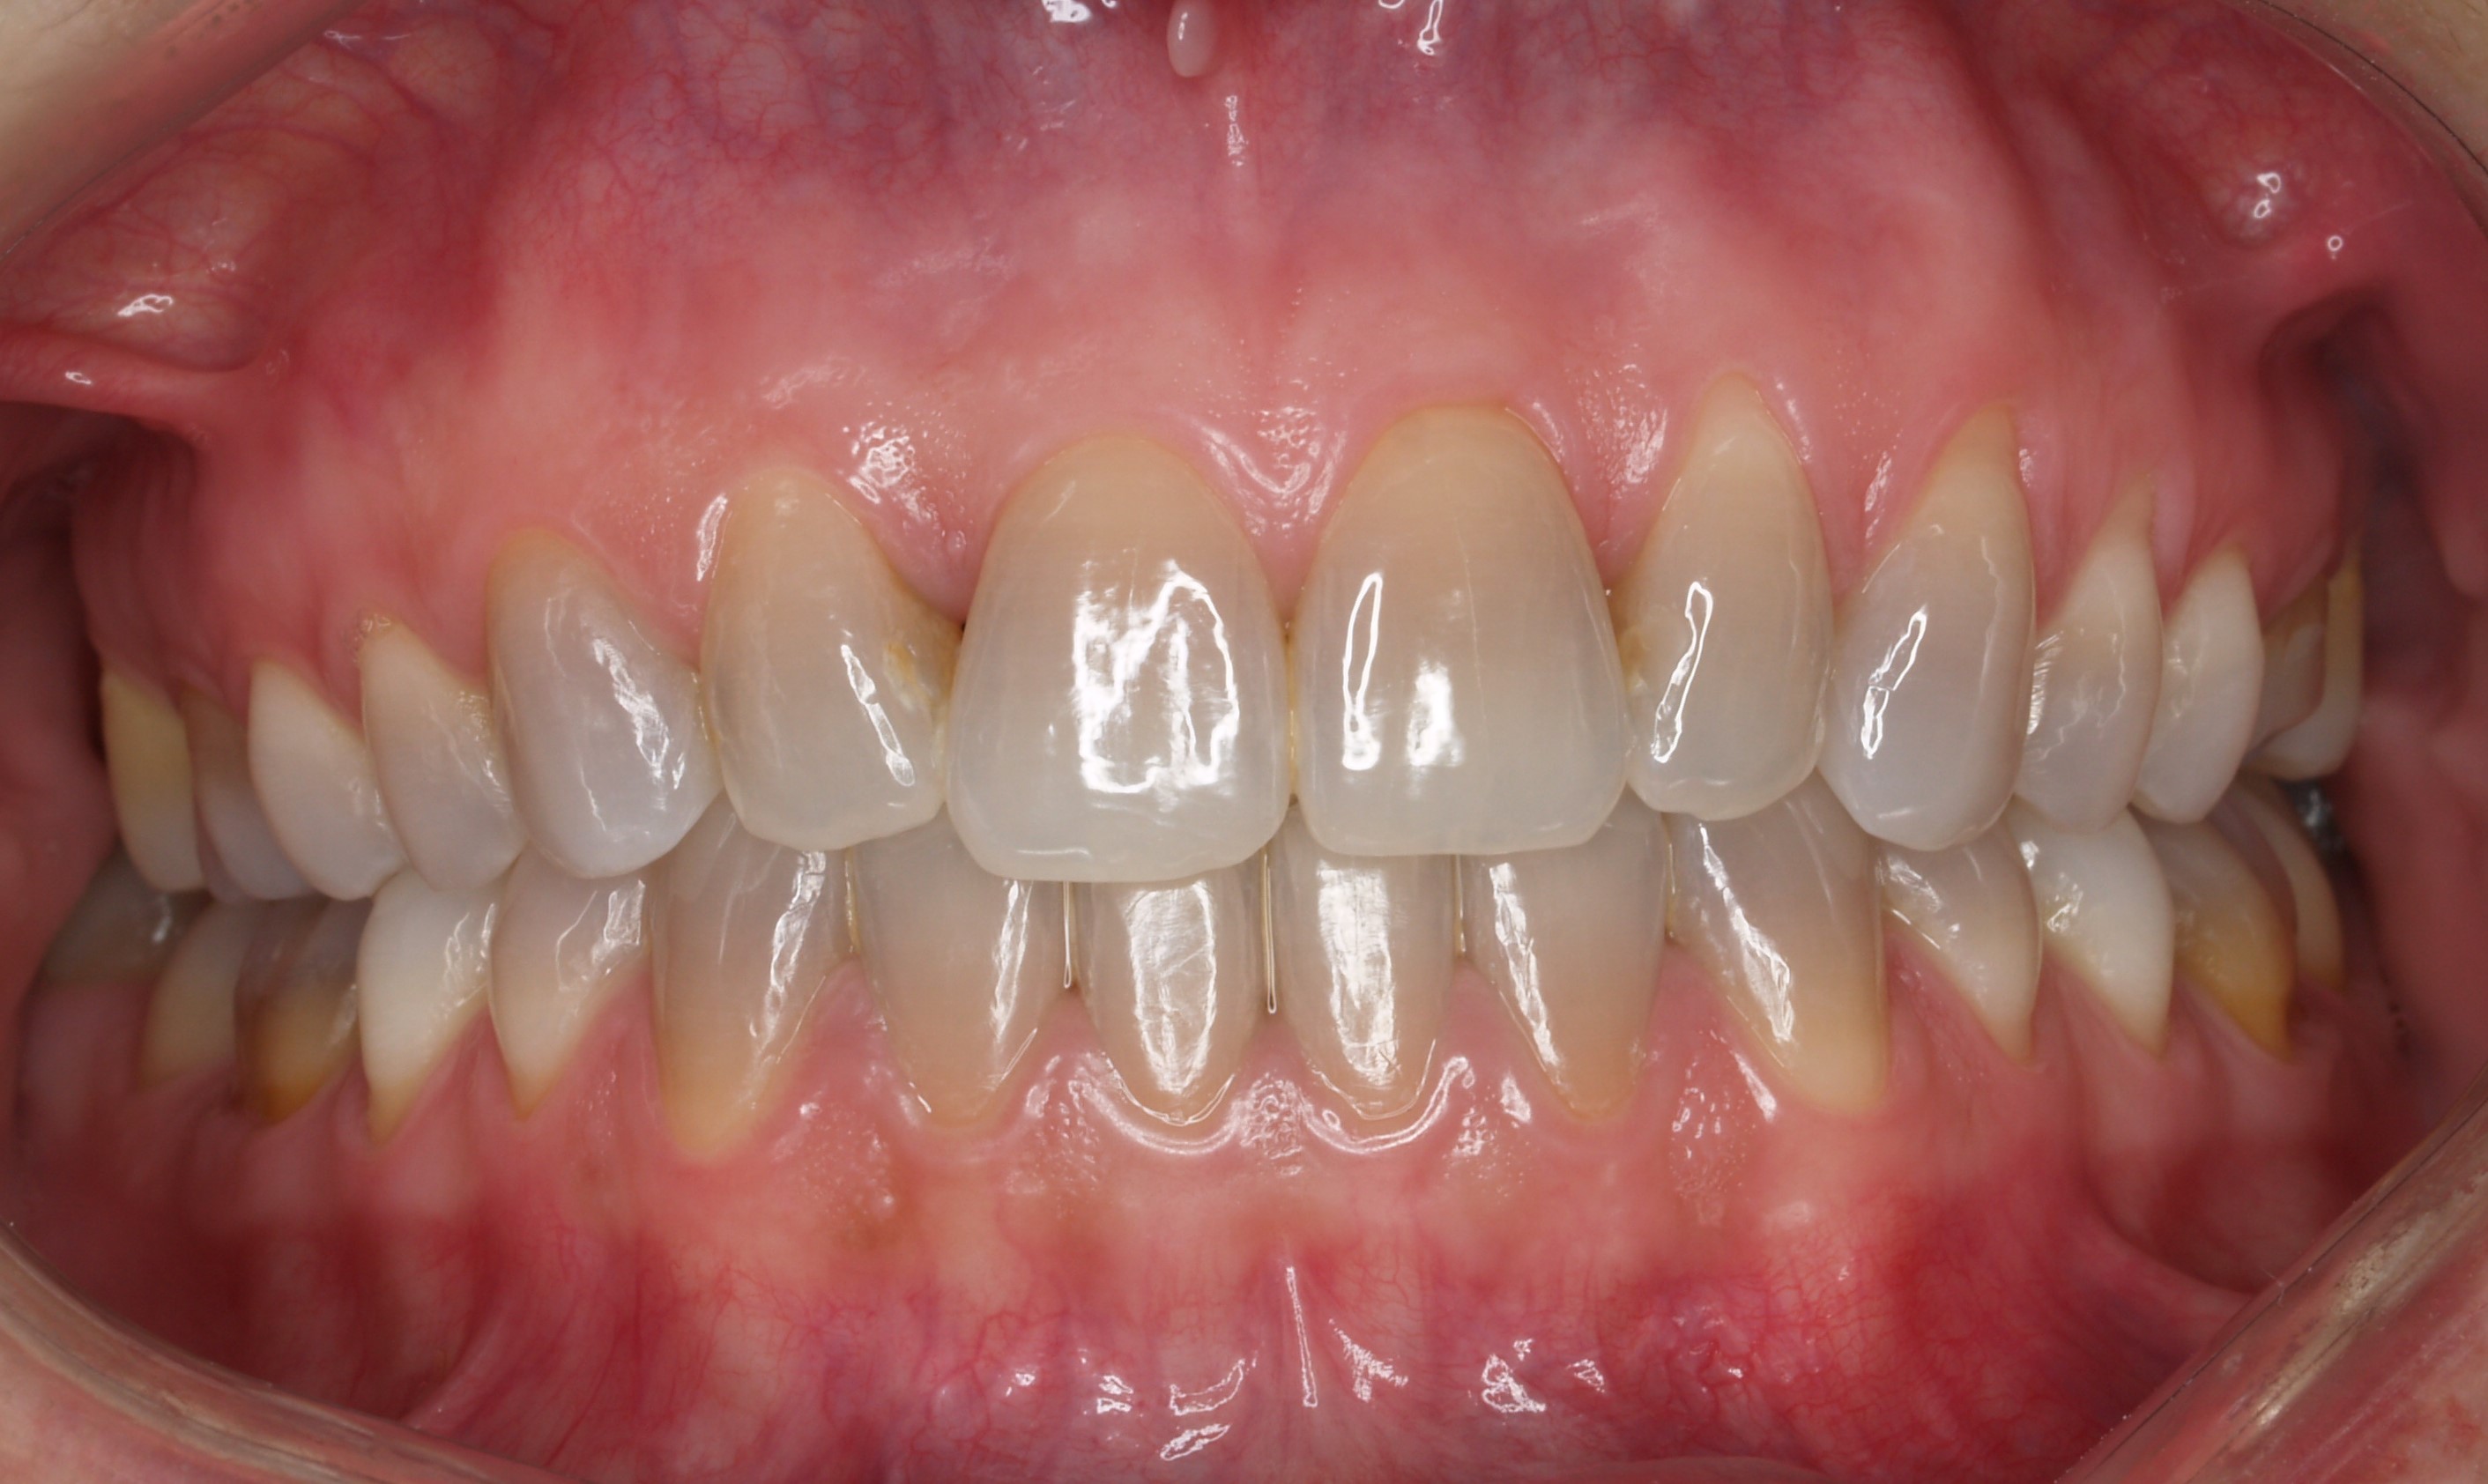

Carillas de composite

Carillas de composite - Antes Carillas de composite - Después

ANTES

DESPUÉS